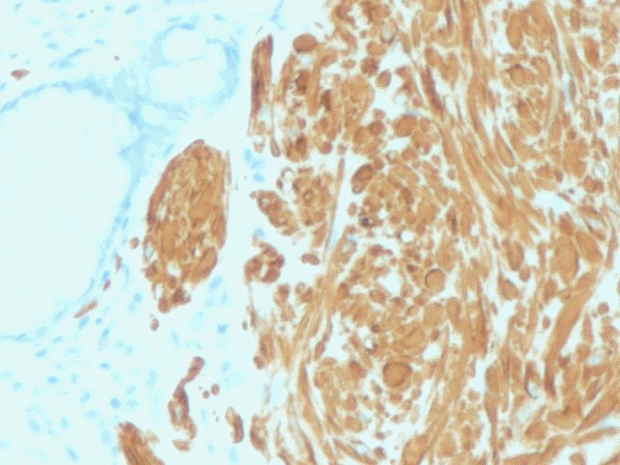

A 47-year-old man came to the health center for a general medical checkup. He did not have any gastrointestinal symptoms. Vital signs were stable. Laboratory examination showed no abnormal findings except elevated triglyceride and low-density lipoprotein cholesterol. Abdominal sonography revealed fatty liver. Chest X-ray and urine examination showed no abnormal findings. Upper endoscopy showed reflux esophagitis. Colonoscopy exam revealed a protruded type polyp measuring 8 mm (Fig. 3) and submucosal injection with polypectomy was done with snare (Boston Science). The surface of the polyp appeared pale with sharp demarcation from the surrounding normal mucosa. Leiomyoma was confirmed by pathology (positive for desmin and negative for c-kit) (Figs. 4 and 5). Leiomyoma arising from the muscularis mucosa was confirmed by pathology and it was removed completely grossly and pathologically.